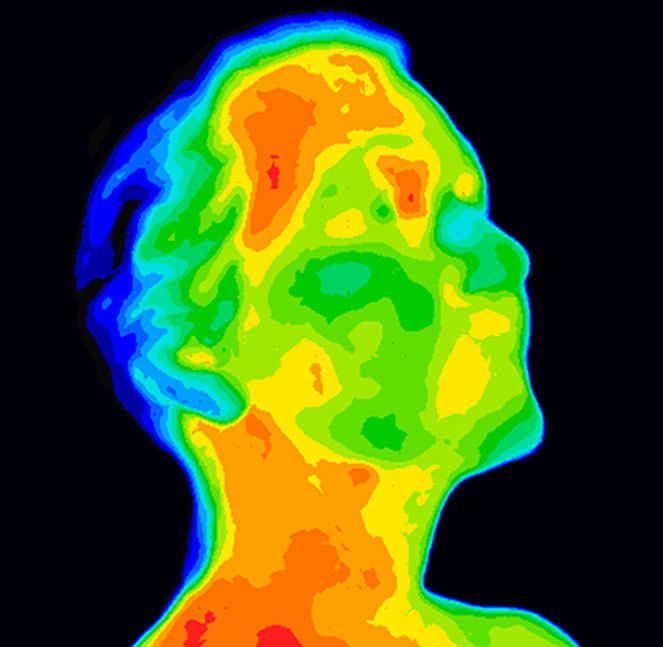

若物体的发射率已知,则可以根据物体发射红外能量的多少来确定物体的温度。人体发出的红外辐射峰值波长通常大约为 9µm。1 温度的变化会导致发射的红外辐射发生变化,热成像系统由此可以在受检测者的体温超出正常范围时予以识别(图 1)。